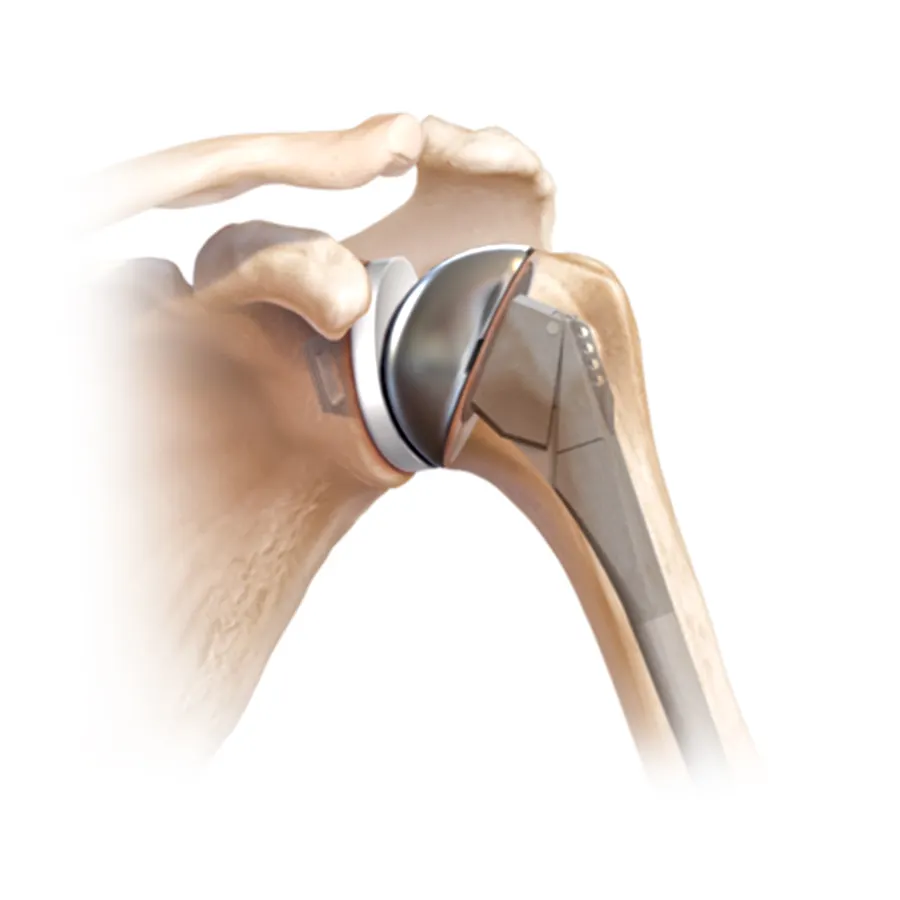

Joint Replacement

surgeries performed

Most trusted, advanced, and affordable knee, hip, elbow, limb salvage surgery in India.

Dr Mujahid Saleem is an eminent Orthopaedic surgeon specialising in Joint Replacement Surgery, has exceptional Diagnostic and surgical skills operating now for over 35 years he has performed more than 20,000 surgeries using state-of-the-art techniques for optimum and functional recovery of his patients.